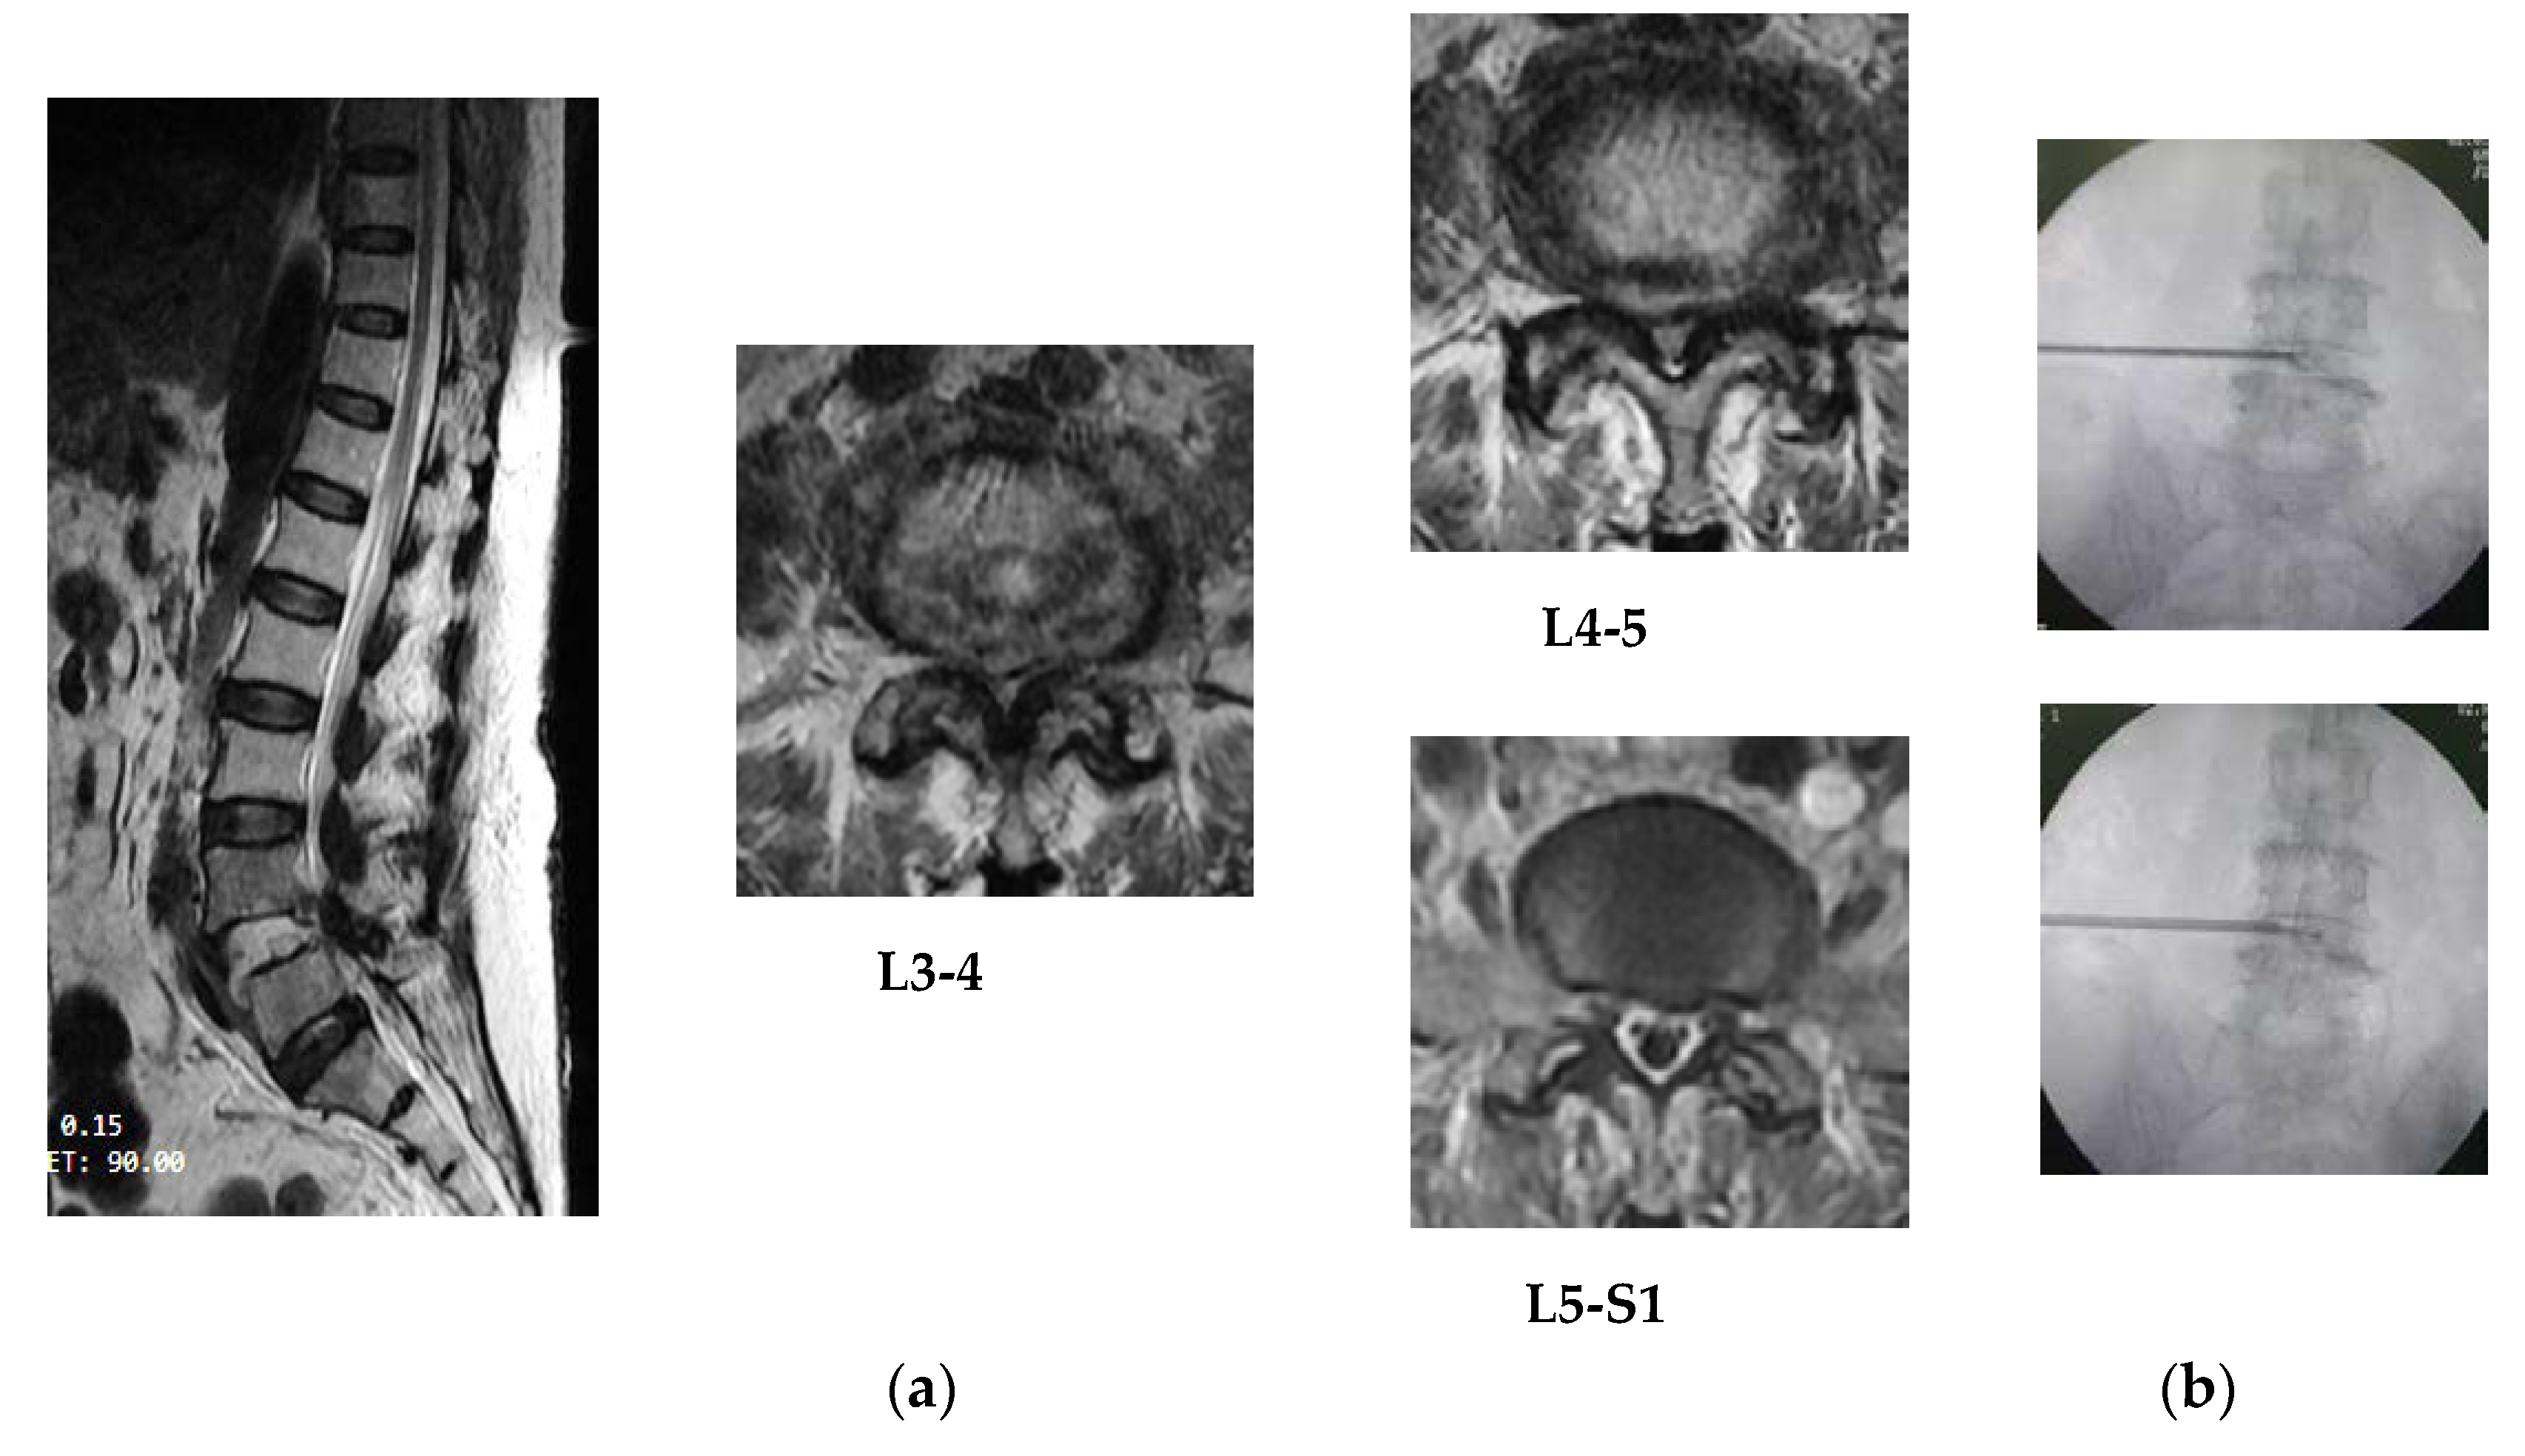

Figure 4. (a) MRI result of patient #3 showed extruded disc on T12-L1 and L3-4 levels and protrusion on L1-2 level by lateral view, posterolaterally protrusion on L1-2 and L3-4 levels and posterocentral compression on T12-L1 level and slightly to the left side by axial view; (b) according to the site of lesion that went to posterocentral and slightly to left side (T12-L1 and L3-4), the dilator canula and discectomy, either bipolar coagulation, had not far to the midline (one-fourth portion between midline and lateral border of disc) by PA view.